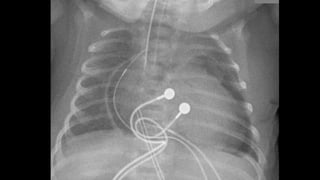

Pneumotórax

Pneumotórax hipertensivo